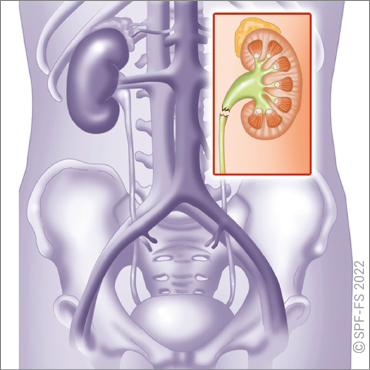

Les reins

Les glandes surrénales